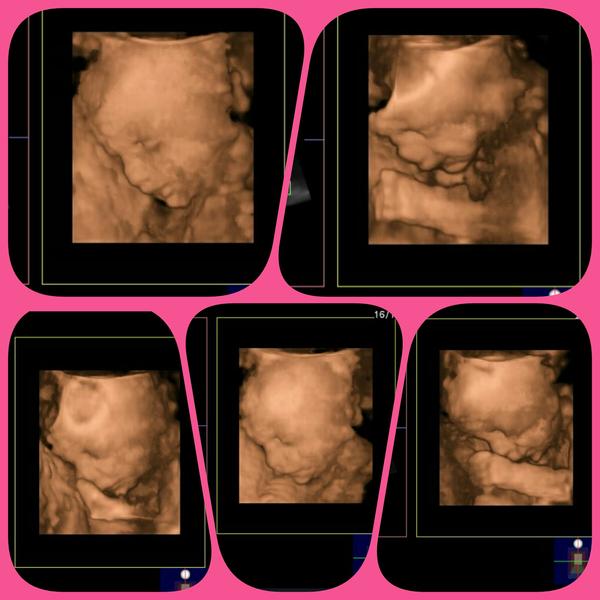

Ahooj Repromeďačky, tak u nás končíme poslední týden 2 trimestru, abysme se mohly s chutí vrhnout na ten 3...poslední 😀 v týdnu jsme byly na 3D ultrazvuku, tak Vám sem hodím foto naší lásky 😍 je to kočka už i v bříšku. Moc se na ni těšíme 😉 tento týden jsme ještě stihly i těhot.cukrovku..